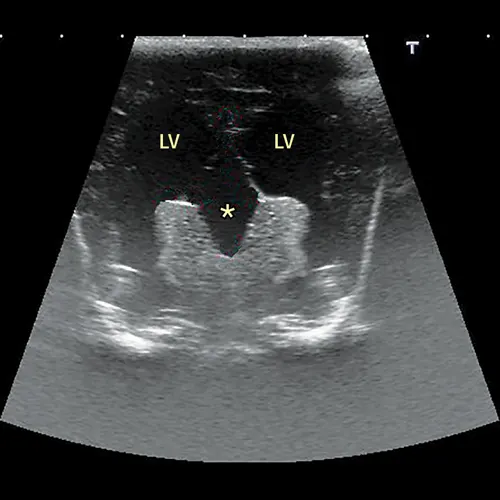

Ultrasound image of brain showing large rounded areas of hypoechogenicity.

FIGURE 3

Transverse ultrasound of the brain obtained through a persistent fontanelle demonstrating enlargement of the lateral ventricles (LV) and a supracollicular collection of CSF (asterisk)